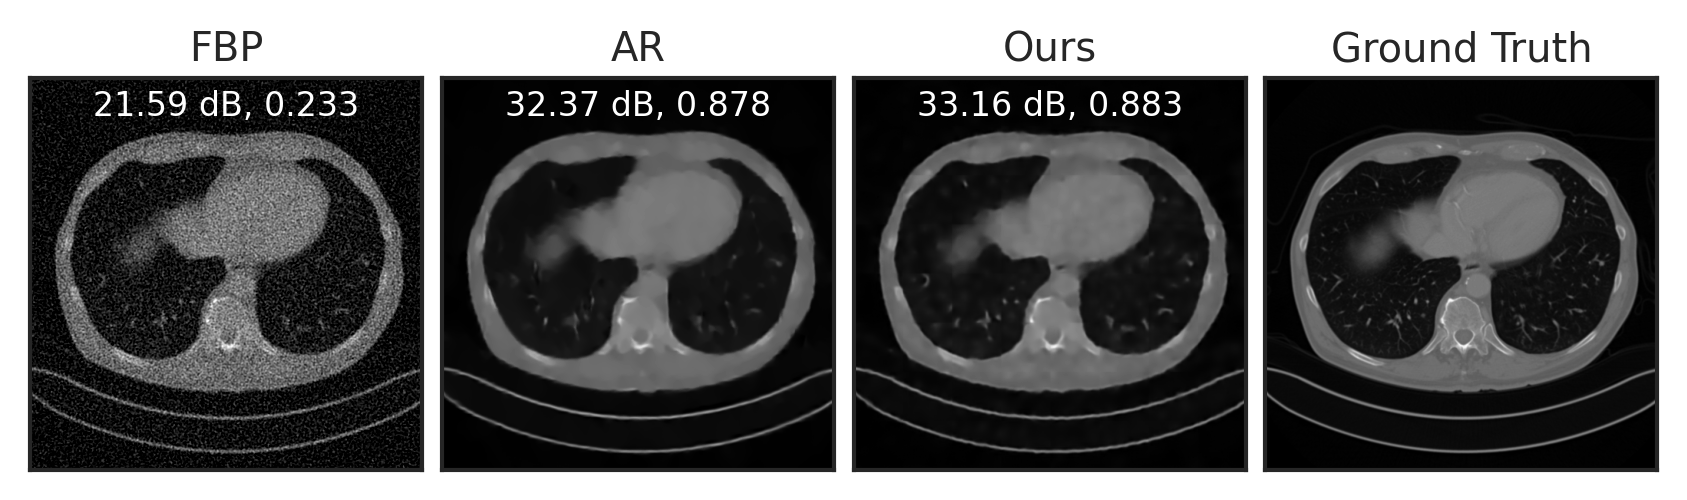

We train LPN on the public Mayo-CT dataset mccollough2016tu of Computed Tomography (CT) images, and evaluate it for two inverse tasks: sparse-view CT reconstruction and compressed sensing. For sparse-view CT reconstruction, we compare with filtered back-projection (FBP) willemink2019evolution, the adversarial regularizer (AR) method of lunz2018adversarial with an explicit regularizer, and its improved and subsequent version using unrolling (UAR) mukherjee2021end. UAR is trained to solve the inverse problem for a specific measurement operator (i.e., task-specific), while both AR and LPN are generic regularizers that are applicable to any measurement model (i.e., task-agnostic). In other words, the comparison with UAR is not completely fair, but we still include it here for a broader comparison.

Following Lunz et al. (2018), we simulate CT sinograms using a parallel-beam geometry with 200 angles and 400 detectors, with an undersampling rate of . See Section E.4 for experimental details. As visualized in Figure 4(a), compared to the baseline FBP, LPN can significantly reduce noise in the reconstruction. Compared to AR, LPN result is slightly sharper, with higher PNSR. The numerical results in Table 2 show that our method significantly improves over the baseline FBP, outperforms the unsupervised counterpart AR, and performs just slightly worse than the supervised approach UAR—without even having had access to the used forward operator. Figure 4(b) and Table 2 show compressed sensing results with compression rates of and . LPN significantly outperforms the baseline and AR, demonstrating better generalizability to different forward operators and inverse problems.